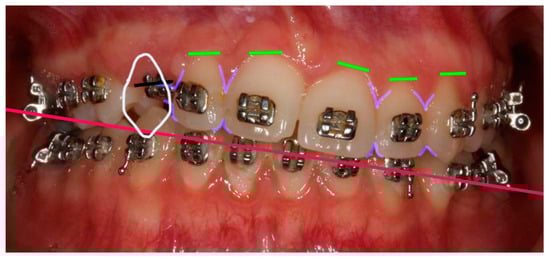

Figure 4. Smile Design. In white, shape of # 23 in position of # 13: the mesio-distal space available for the # 13 tooth is considerably larger than the mesiodistal size of # 23. In lilac, gingival and cervical embrasure spaces: there are considerable discrepancies in the embrasures’ form in the vicinity of # 13. In green, gingival zenith of the anterior teeth showing considerable alignment discrepancies. In red, aesthetic plane, clockwise canted.

A Photoshop Smile Design (PSD, Adobe Photoshop, Adobe, Saint Jose, California, CA, USA) [8] was presented to the patient (Figure 4). The patient was informed of the limitations associated with the present treatment, particularly regarding the aesthetic outcomes. Indeed, the reduced size of the papilla between # 12 and the future # 13, in conjunction with the bone level of the edentulous ridge apical to the cementoenamel of # 12, could have resulted in the persistence of a black triangle. The different mesio-distal diameter of teeth # 13 and # 23 was also considered.

The initial correction of the iatrogenic occlusal plane cant was conducted through orthodontic means, utilising a mandibular temporary anchorage device (TAD) and the ankylosed canine as anchorage points, with the application of extrusion and intrusion mechanics (Aarhus miniscrew, American Orthodontics, Sheboygan, WI, USA; Victory Series brackets, 3M, Saint Paul, MN, USA). The sagittal component of the malocclusion was not addressed in order to reduce the overall treatment time and to avoid exacerbating the existing root resorptions (Figure 3).